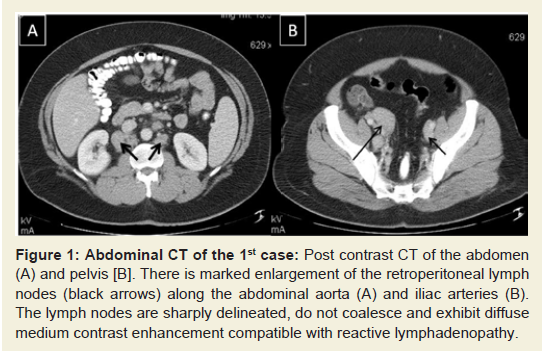

Lymphadenopathy is a relatively common manifestation of connective tissue diseases (CTD), particularly rheumatoid arthritis [1-4], and systemic lupus erythematosus (SLE) [4-7]. The clinically palpable nodes are predominantly located in the axillary and cervical areas and are usually non tender and discrete, varying in size from a few millimeters to 3-4 centimeters. However, massive abdominal/retroperitoneal lymphadenopathy, as a manifestation of the disease itself, is extremely rare and very few cases have been described so far [8,9]. When such a massive lymphadenopathy, especially in the abdomen, is encountered in a CTD patient, the physician’s main concern is to rule out infectious causes [10-16], granulomatous diseases [17], but also malignant, and rarely benign [18-22], lymphoproliferative disorders. We present herein two patients with CTD, one with SLE and the other with mixed connective tissue disease (MCTD), in whom massive abdominal lymphadenopathy was directly related to activity of the underlying disease and not to another cause. The purpose of this presentation, besides reporting a very rare manifestation of CTD activity, is the sensitization of the physician to this rare occurrence which should be included in the differential diagnosis of similar cases, without of course underestimating the importance of prompt and appropriate study to rule out other more serious possibilities.2nd Case: A 47 year old Caucasian lady was diagnosed with MCTD 11 years ago, on the basis of interstitial lung disease (ILD), symmetric polyarthritis, myositis with elevation of muscle enzymes and compatible electromyographic findings, Raynaud’s phenomenon and high titre anti-U1RNP Abs. During the first 2 years after diagnosis, she had received six monthly IV cyclophosphamide pulses and IV methylprednisolone pulses, for treatment of her ILD with favourable response (improvement of pulmonary function and HRCT picture). In early 2005, during an episode of diarrhea, which lasted for 10 days, appropriate investigation including endoscopy did not show findings suggestive of inflammatory bowel disease (IBD) or another specific pathology. This disappeared without modification of her low dose steroid treatment (5mg of prednisone daily). For the next 5 years on regular follow up on an outpatient basis, she had been feeling well on this regimen. In April 2010, she presented with mild-moderate arthritis in the small joints of her hands and atypical abdominal pain, accompanied by elevated serum indices of inflammation. SACE level was normal. Because of the previously suspected IBD, a new lower gastrointestinal endoscopy was performed which was unrevealing. An abdominal CT though showed multiple enlarged lymph nodes, with a diameter more than 3cm along the iliac vessels bilaterally (Figure 3). No other pathology of the abdominal organs was seen, while a chest CT showed no significant findings. In order to exclude a lymphoproliferative process - that might have been related to the previously administered cyclophosphamide - or a specific infection such as extrapulmonary tuberculosis - in view of a positive PPD skin test that the patient exhibited-, she underwent laparoscopic lymph node biopsy. The histologic diagnosis was reactive lymphadenitis with follicular hyperplasia (Figure 4). Appropriate stains and cultures did not reveal any infectious agent, whereas immunohistochemistry ruled out a lymphoproliferative process. On the basis of the above, the whole picture was attributed to the patient’s underlying CTD. She improved immediately after increasing the dose of prednizone to 20 mg/d with prompt resolution of the arthritis and disappearance of the abdominal pain. At the same time, the patient was placed on antituberculous chemoprophylaxis for six months with isoniazid because of the positive PPD skin test. Since then she has remained asymptomatic with gradual decrease of prednisone dose to 5 mg/d, whereas an abdominal MRI has shown reduction in the size of the lymph nodes.